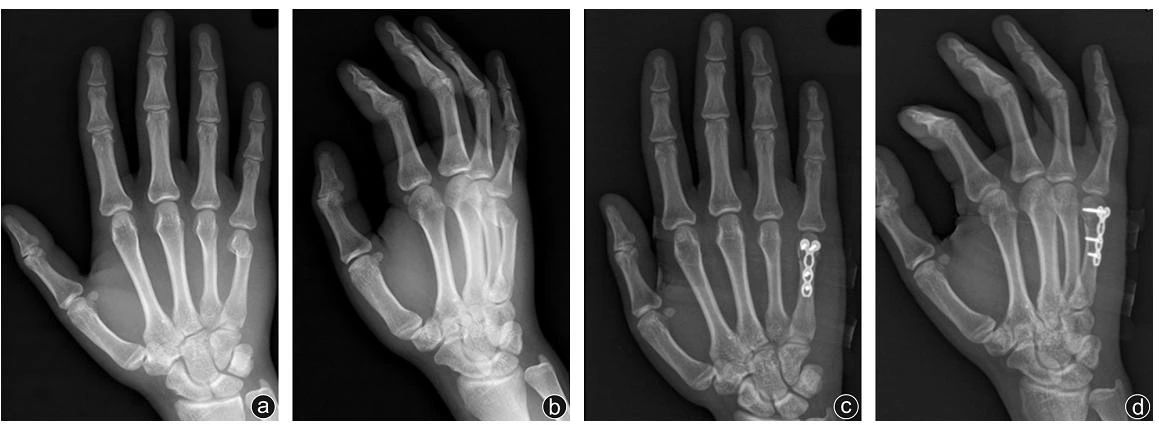

На снимке выше показан пациент с переломом шейки пятой пястной кости правой руки, которому была проведена операция по мыщелковой пластине АО с мини-замком.

На предоперационной переднезадней рентгенограмме (а) и косой рентгенограмме до операции (б) выявлен перелом шейки пятой пястной кости правой руки; послеоперационная переднезадняя рентгенограмма (в) и послеоперационная косая рентгенограмма (г). Видно, что перелом зажил и внутренняя фиксация установлена. (из ссылки 4)